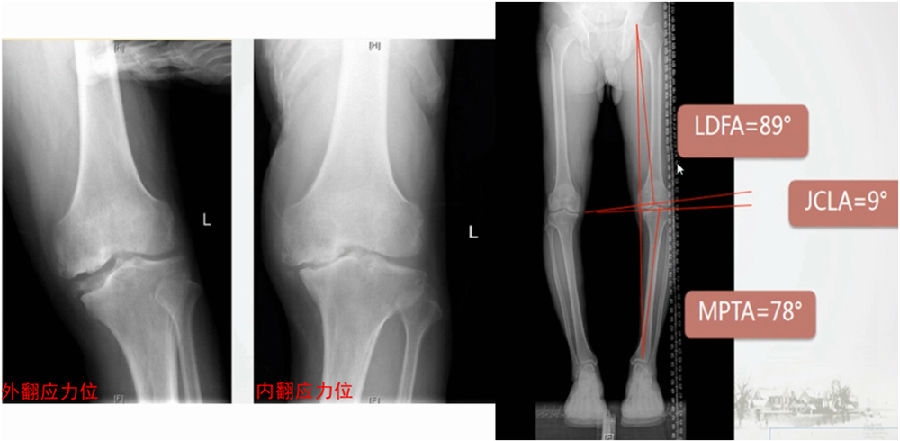

通过MAT测量全长片和内外侧应力位片,可以明确的测量出畸形的来源是股骨还是胫骨,有没有关节内磨损和韧带松弛。

膝MCOA病例,对线异常来源多个因素:胫骨畸形(MPTA异常),股骨形(mLDFA异常),胫骨平台塌陷,LCL松弛,内侧关节软骨丢失造成关节线不等宽等。MAT可以确定其中每种成分;应力下拍片,确定JLCA的关节松弛成分。关节软骨丢失占JLCA 3度,LCL松弛占JLCA 4度。